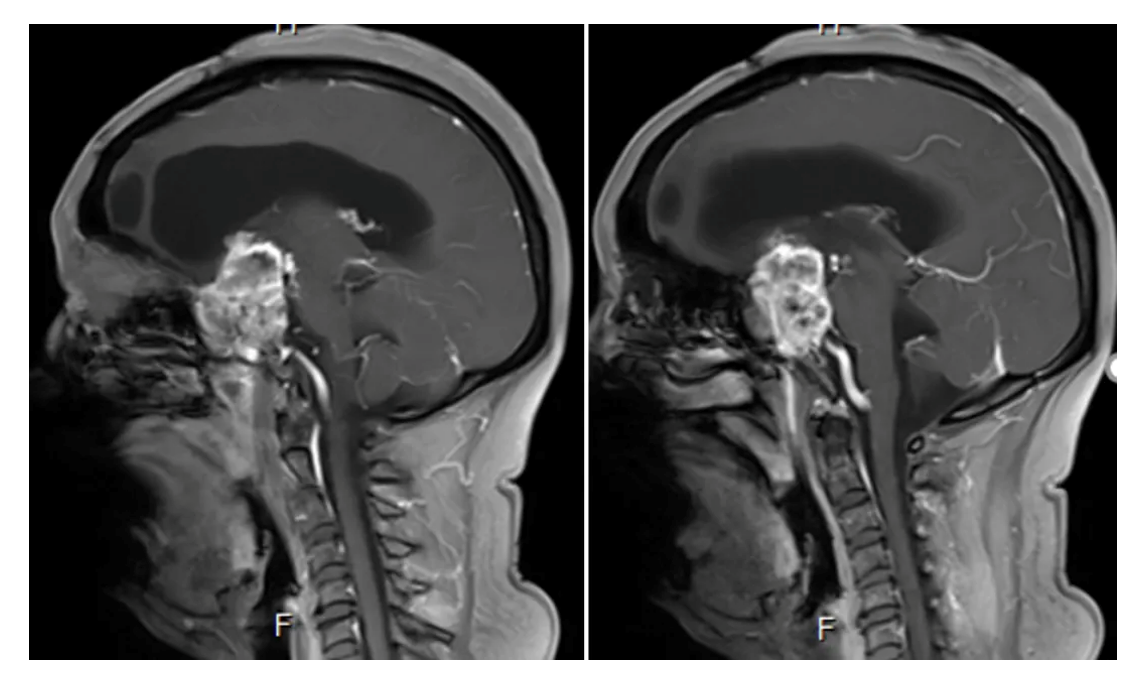

Cranial MRI enhanced

2. Enhanced axial and coronal-sagittal views showed that the tumor was unevenly enhanced, which was located in the saddle region, invaded the right cavernous sinus, and encircled the internal carotid artery and its branches and perforating vessels.

Postoperative MRI enhancement: Showing a major resection of the tumor